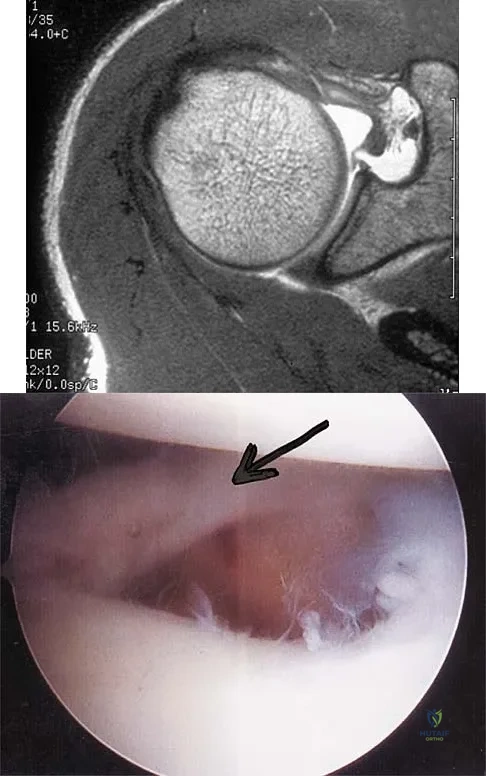

Question 5

A patient has right shoulder pain. Figure 1a shows a gadolinium-enhanced transverse MRI scan at the level of the coracoid. Figure 1b shows an arthroscopic view of the anterior structures from a posterior portal. These images reveal which of the following findings?

Explanation